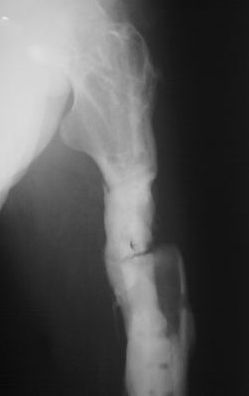

В настоящее время госпитализирован для оперативного лечения по поводу

рефрактуры на уровне верхней трети бедренной кости. Планируется остеосинтез аппаратом

Илизарова с стержневой модификации (без обширного вмешательства в зоне перелома)и как

вариант тунеллизации через зону перелома с возможным введением в

каналы "Коллапана", "Сhronos" и.т.п. Также были предложены варианты

пластинками с угловой стабильностью, блокируемый остесинтез гвоздями.

Движения в коленном суставе до повторного перелома сгибание 90

градусов, разгибание 180. Пациент пониженного питания. Какие есть